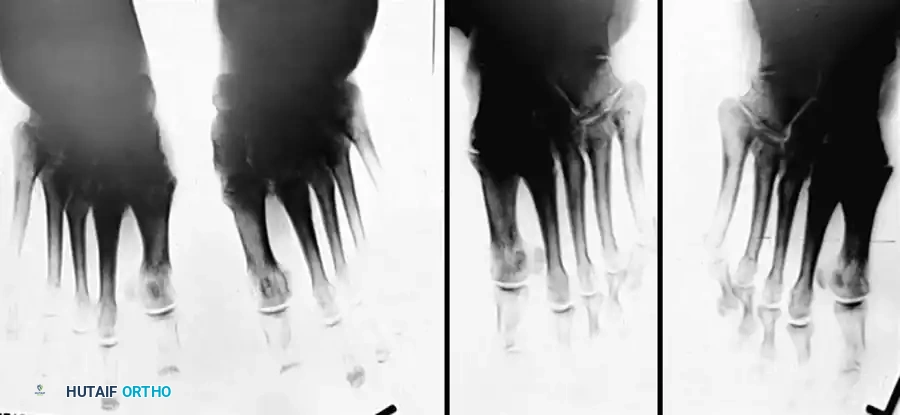

Clinical Pearl: The loss of the medial longitudinal arch can occur at the talonavicular, navicular-cuneiform, or cuneiform-metatarsal articulations. A weight-bearing lateral radiograph may initially show no bony collapse, appearing identical to the asymptomatic contralateral foot, even in the presence of obvious clinical pes planus.

- Clinical Findings: Loss of PTT function resulting in a flexible flatfoot deformity (hindfoot valgus, midfoot abduction). Mild lateral sinus tarsi pain may begin to manifest.

- Radiography: Degenerative arthritic changes are visible in the subtalar and/or talonavicular joints.